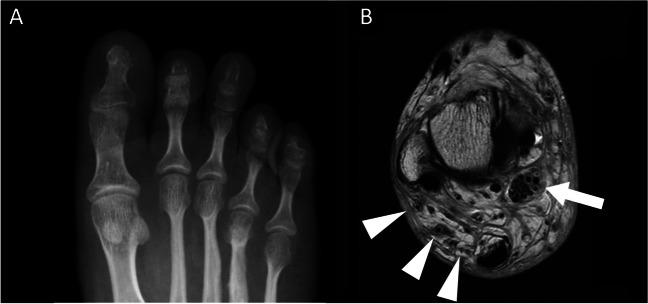

Somatic overgrowth disorders comprise a wide range of rare conditions that present with focal enlargement of one or more tissue types. The PI3K-AKT-mTOR pathway is a signalling pathway that induces angiogenesis and cell proliferation, and is one of the most commonly overactivated signalling pathways in cancer. The PI3K-AKT-mTOR pathway can be up-regulated by genetic variants that code for proteins in this pathway, or down-regulated by proteins that inhibit the pathway. Mosaic genetic variations can result in cells that proliferate excessively in specific anatomical locations. The PIK3CA-related overgrowth spectrum (PROS) disorders include CLOVES syndrome, macrodystrophia lipomatosa, and Klippel-Trenaunay syndrome among many. The neurofibromatosis type 1 (NF1) gene encodes neurofibromin which down-regulates the PI3K-AKT-mTOR pathway. Thousands of pathological variants in the NF1 gene have been described which can result in lower-than-normal levels of neurofibromin and therefore up-regulation of the PI3K-AKT-mTOR pathway promoting cellular overgrowth. Somatic overgrowth is a rare presentation in NF1 with a wide range of clinical and radiological presentations. Hypertrophy of all ectodermal and mesodermal elements has been described in NF1 including bone, muscle, fat, nerve, lymphatics, arteries and veins, and skin. The shared signalling pathway for cellular overgrowth means that these radiological appearances can overlap with other conditions in the PIK3CA-related overgrowth spectrum. The aim of this review is to describe the genetic basis for the radiological features of NF1 and in particular compare the appearances of the somatic overgrowth disorders in NF1 with other conditions in the PIK3CA-related overgrowth spectrum.